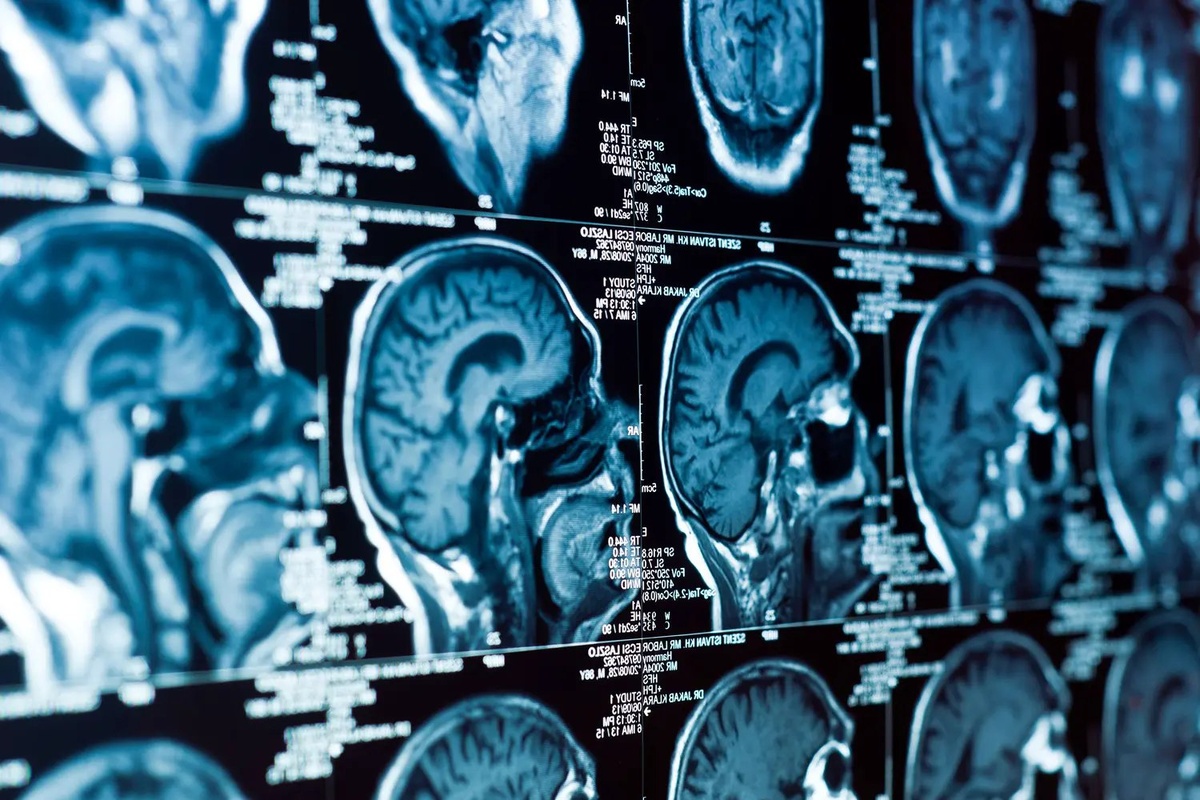

MIT сделала прорыв в лечении ETMR, открыв мишени FGFR и C19MC Ученые MIT нашли слабое место в ужасно агрессивной детской опухоли мозга (ETMR)! Оказалось, что клетки опухоли общаются друг с другом, и если прервать их «болтовню», то рост опухоли можно остановить. Уже есть первые успехи с лекарством, блокирующим один из «каналов связи», а дальше будут испытывать комбинацию лекарств и воздействие на ген C19MC. Короче, надежда на победу над ETMR появилась! 🗞 Подробнее: fabrec.ru 🏞 Фото от: www.gazeta.ru 🔔 Подписывайтесь на нас: fabrec_press

Ученые MIT нашли слабое место в ужасно агрессивной детской опухоли мозга (ETMR)! Оказалось, что клетки опухоли общаются друг с другом, и если прервать их «болтовню», то рост опухоли можно остановить. Уже есть первые успехи с лекарством, блокирующим один из «каналов связи», а дальше будут испытывать комбинацию лекарств и воздействие на ген C19MC. Короче, надежда на победу над ETMR появилась!